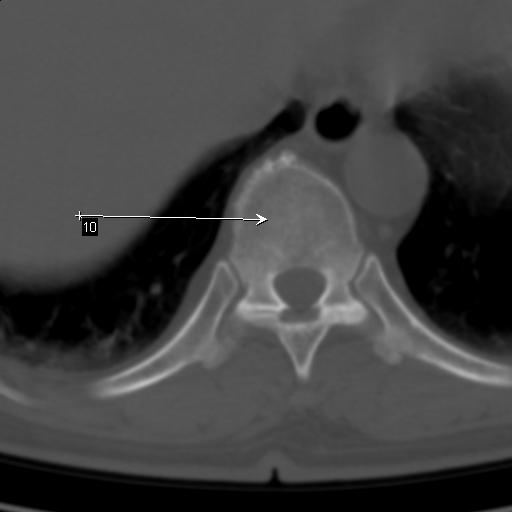

标题: CT25189:胸椎ct,请会诊!

既往食管癌,现行ct检查!

中上段食道癌,椎体轻度退变。

支持中上段食道癌,椎体轻度退变,必要时做ect。